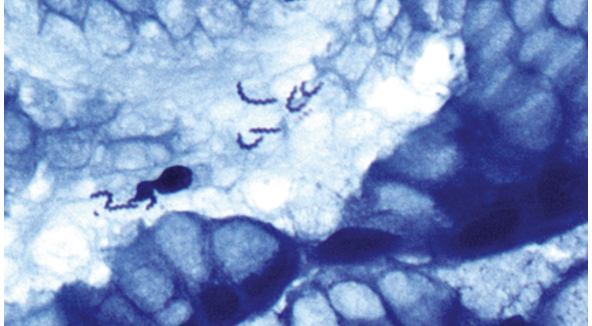

1) giardia lamblia

2) intestin grêle

3)

Normale ou aplatissement des villosités

Giardia dans la lumière

Si absence de plasmocytose dans le chorion, rechercher CIVD